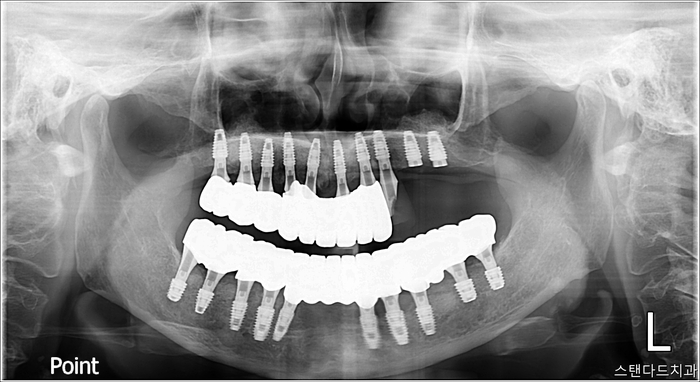

최종보철체결 / 마무리

촬영:2024년12월17일

최종보철 마무리되었습니다.

1년간의 긴 여정이었습니다.

기간적으로는 1년이라는 시간에 걸쳐 마무리가 되었지만

사실상 가장 끝 어금니 임플란트만

7개월 차에 진행되어

대다수의 보철인 전체 임플란트는

6개월 만에 마무리가 됐다고 봐도 무방합니다.

최종보철은 12월에 마무리되었지만(상악 2개 포함)

6개월 차부터 상악 2개를 제외한

나머지 임플란트는 최종보철로 지내오신지라